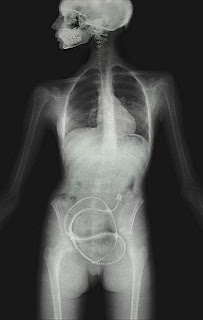

La teniasis es una enfermedad parasitaria intestinal causada por las formas adultas de cestodos  del género Taenia. En el ser humano la teniasis es producida por Taenia solium o Taenia saginata, comúnmente conocidas como "lombrices solitarias", porque, dado su gran tamaño, suele encontrarse un único individuo parásito en el intestino de las personas infestadas. Las tenias, cuyos adultos son hermafroditas, requieren de un huésped intermediario para cumplir su ciclo biológico: el cerdo y el jabalí, en el caso de la Taenia solium, y el ganado vacuno para la Taenia saginata. El ser humano puede ser también hospedero accidental del metacestodo, es decir la forma larvaria o intermedia de la T. solium, en cuyo caso se desarrolla la enfermedad conocida como cisticercosis.

Cuando hay una cisticercosis, los síntomas dependerán del órgano afectado y de la cantidad de quistes existentes y pueden llegar a manifestarse después de mucho tiempo de adquirido el parasito:

• Si se localizan bajo la piel, en los músculos, se presentan como bolitas que son fácilmente palpables.

•  Cuando afectan los ojos, ocasionan visión borrosa o turbia, disminución o pérdida de la capacidad visual. El cisticerco generalmente se localiza en el humor vítreo, retina, conjuntiva y órbita ocular y puede llegar a desprender la retina, lo que llevará a la ceguera.

•  Cuando los cisticercos afectan el cerebro, los síntomas son: convulsiones, hidrocefalia (inflamación del cerebro), alteraciones de la conducta parecidas a las de la esquizofrenia o paranoia, pérdida de la memoria, neurosis, confusión, meningitis, epilepsia, dolor de cabeza y otros problemas más.

•  Si se alojan en la columna vertebral, las manifestaciones pueden ser trastornos de la marcha, dolor, parálisis u otros síntomas neurológicos.